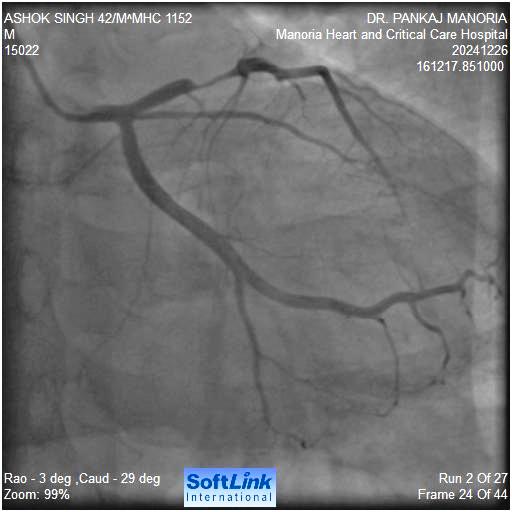

53/ M presented with unstable angina Echo showed normal LV function He had raised serum creatinine 2.5 mg % and eGFR was 18 CAG showed a single vessel disease with proximal LAD 90 % stenosis plan was to do a absolute zero contrast PCI using LIVE IVUS technique

Relevant Catheterization Findings